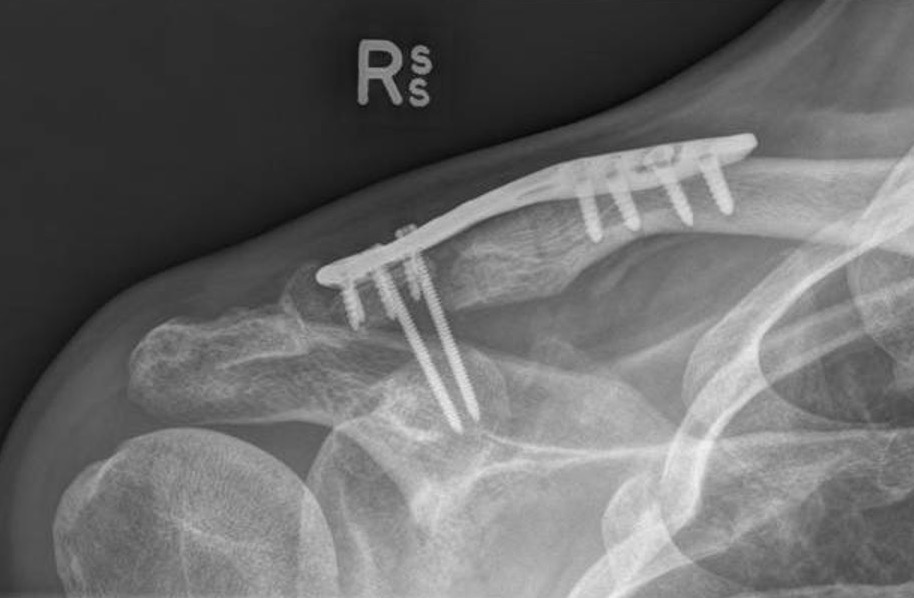

Hook plate

Technique

Reduction of ACJ

- hook under posterior acromion

- allows CC ligaments to heal

- need to remove plate at 4 - 6 months

Risks

Subacromial erosion - may be reduced by increasing the angle on the hook

Hook plate cut out through acromion - need to remove hook plate at 6 - 8 weeks

Clavicle fracture at end of plate

Results

Hemmann et al Arch Orthop Trauma Surg 2021

- 99 patients with acute ACJ dislocation treated with hook plate

- average loss of reduction of 4 mm after hook plate removal

- nearly all good to excellent outcome

- 68% full ROM post operatively

Kim et al J Orthop Trauma 2021

- 35 patients treated with hook plate

- CT showed average 5 mm of subacromial erosion (50% acromial thickness)